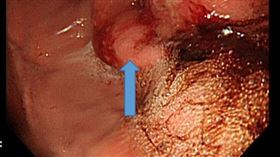

多圖/慎入!大腸癌「真面目」長這樣

大腸直腸癌的發生率越來越高,每年台灣約有一萬四千人被...